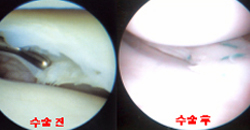

- 관절경 시술의 실례

관절경 수술 기구와 관절경을 통해 무릎 인대재건술을 시행하는 모습

- 전방십자인대 파열

십자인대 파열로 무릎관절의 불안정성이 발생한 경우 관절경으로 인대 재건술을 시행합니다.